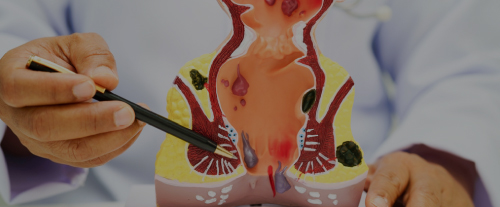

Hemorroides

Diagnóstico y tratamiento clínico

y quirúrgico especializado.